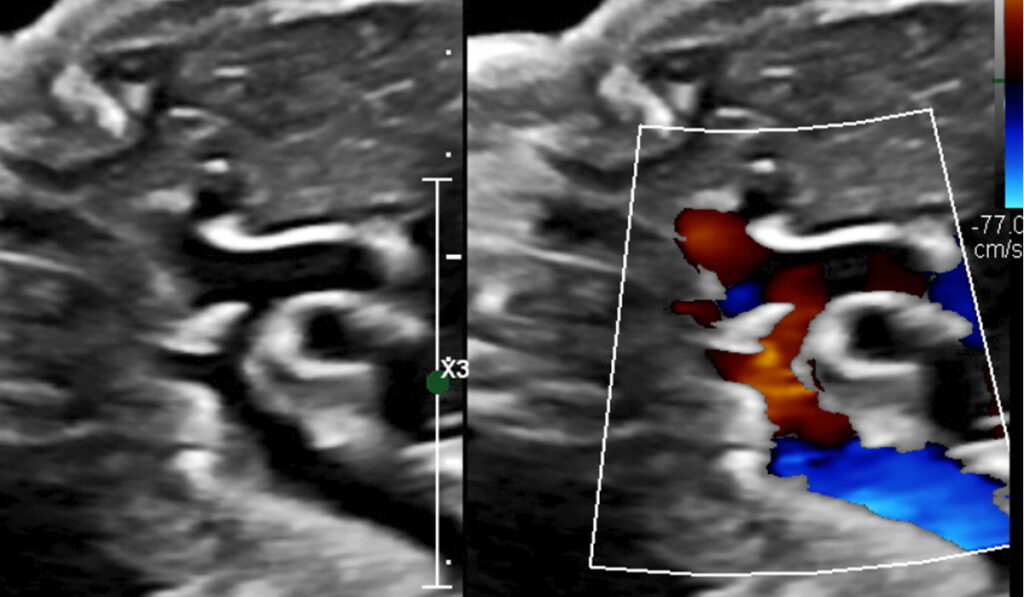

How a Rare Pseudoaneurysm Escaped Misdiagnosis

Echogenic mass seen in prenatal echocardiogram mimics a benign rhabdomyoma.